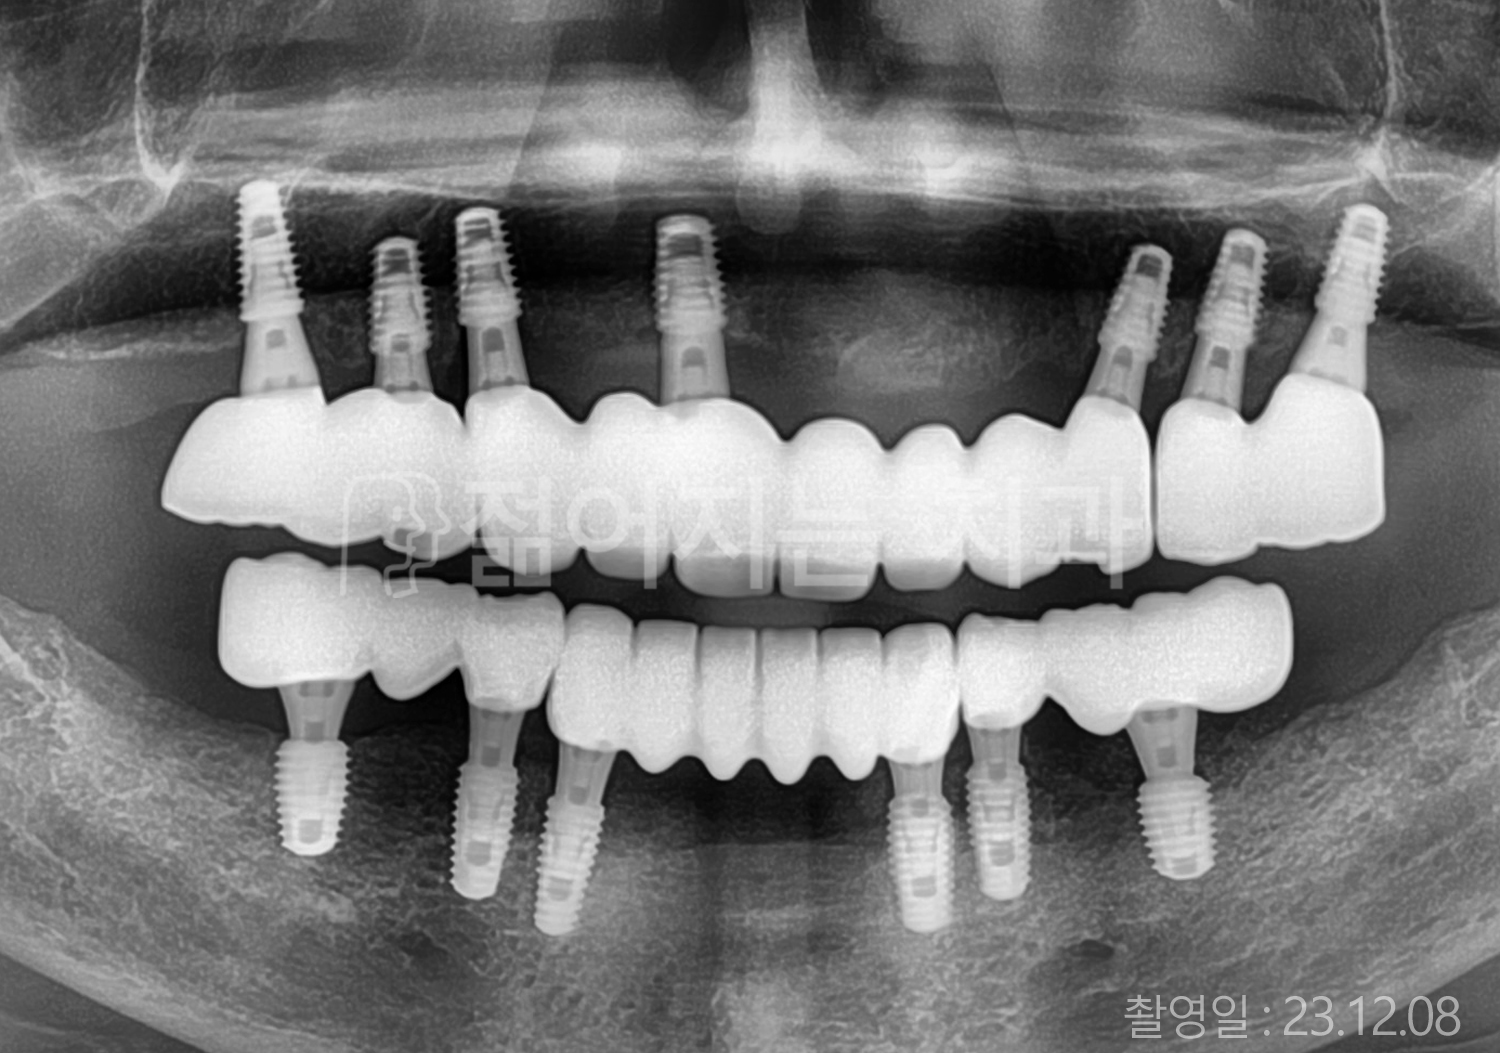

• 60대 전체치아 10개 이상 임플란트